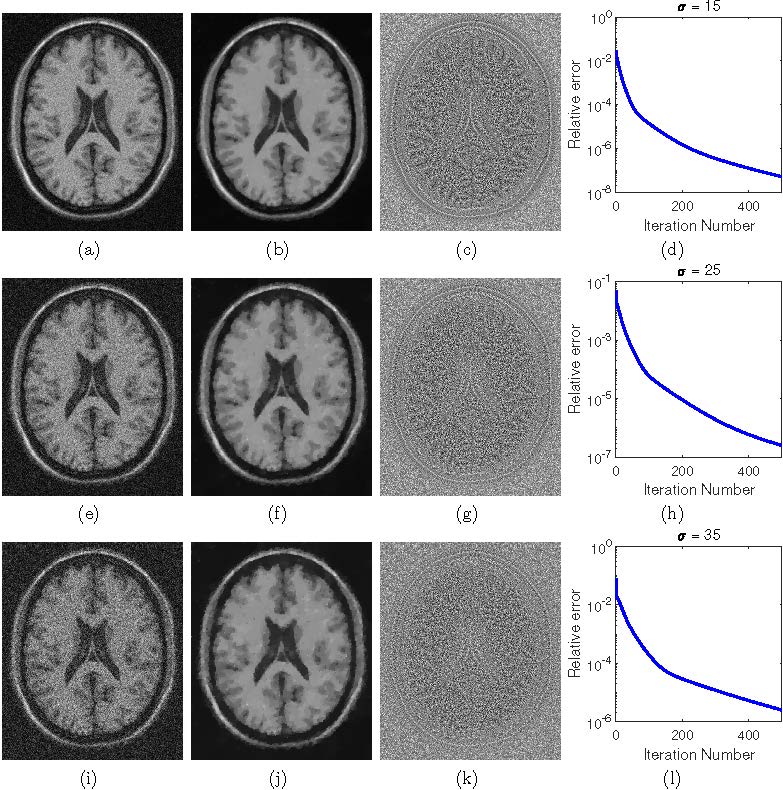

日前,数学科学学院智能计算与交叉科学团队刘志方博士和常慧宾研究员及其合作者在SIAM Journal on Imaging Sciences发表了题为“Variational Rician Noise Removal via Splitting on Spheres”的学术论文。

磁共振成像在医学图像处理中有着广泛的应用。含噪声的磁共振数据通常建模为Rician分布。因此,通常把从含噪声的磁共振图像中估计出干净图像的过程称为Rician噪声去除。由于Rician噪声对信号的依赖性,直接提取干净图像具有很大的挑战。该文提出了一种新的变分方法来去除磁共振成像中的Rician噪声。该文首先探讨复值图像(complex images)的高斯噪声去除和幅度图像(magnitude images)的Rician噪声去除之间的联系,然后通过信噪分离建立约束优化模型。该文中的模型不同于以往的基于最大后验概率的模型,后者使用Rician分布概率密度函数建模,不可避免地包含复杂的贝塞尔函数,导致模型求解时需要很高的计算成本。该文采用能保证收敛的交替乘子方向法求解所提出的球面约束优化模型。与现有变分方法的数值比较表明,该文方法在图像恢复质量方面效果相当,但平均节省了约50%的总计算成本。